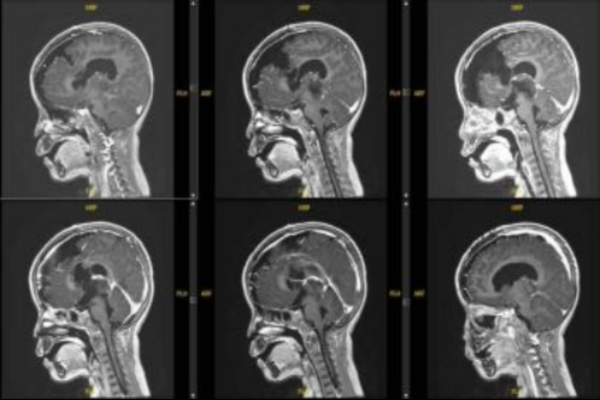

据悉,该患者4岁6个月,其症状为双上肢震颤、右侧踝阵挛。院外头颅MRI平扫示松果体区占位性病变并梗阻性积水、间质性脑水肿。在上海儿童医学中心张江院区神经外科进一步行头颅MRI平扫+增强检查,于松果体区见团块样占位,大小约29.4*26.7*26.5mm,T1WI低信号,T2WI稍高信号,有明显不均匀强化。影像学诊断为右侧丘脑至松果体区占位,考虑恶性肿瘤。

术后病理考虑为颅内间叶源性肿瘤,非脑膜上皮来源。FISH提示EWSR1不典型断裂阳性。术后MRI显示肿瘤完全切除。目前患儿情况稳定,由ICU转入普通病房。

患儿术后MR影像:松果体区肿瘤组织切除完全